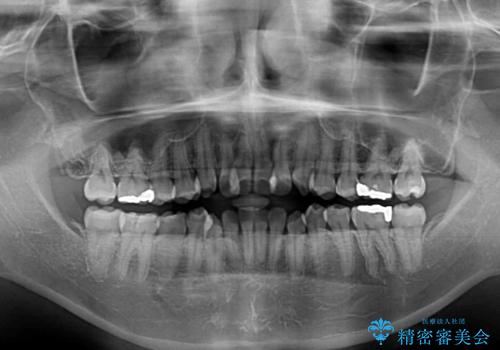

- 前歯のデコボコを気にして来院された患者様です。

前歯のデコボコはもちろん気になるところですが、舌の突出癖により上下前歯が非接触となっている状態でした。

上下前歯が非接触である開咬は、インビザラインによる治療がお勧めではありますが、しっかりと使う自信がないとのことで、ワイヤー装置にて治療を行うこととしました。

デコボコはあっという間に改善されましたが、開咬の改善に時間がかかりました。

舌の突出癖改善のトレーニングをしっかりと行っていただき、上下前歯が接触する咬み合わせを達成することができました。